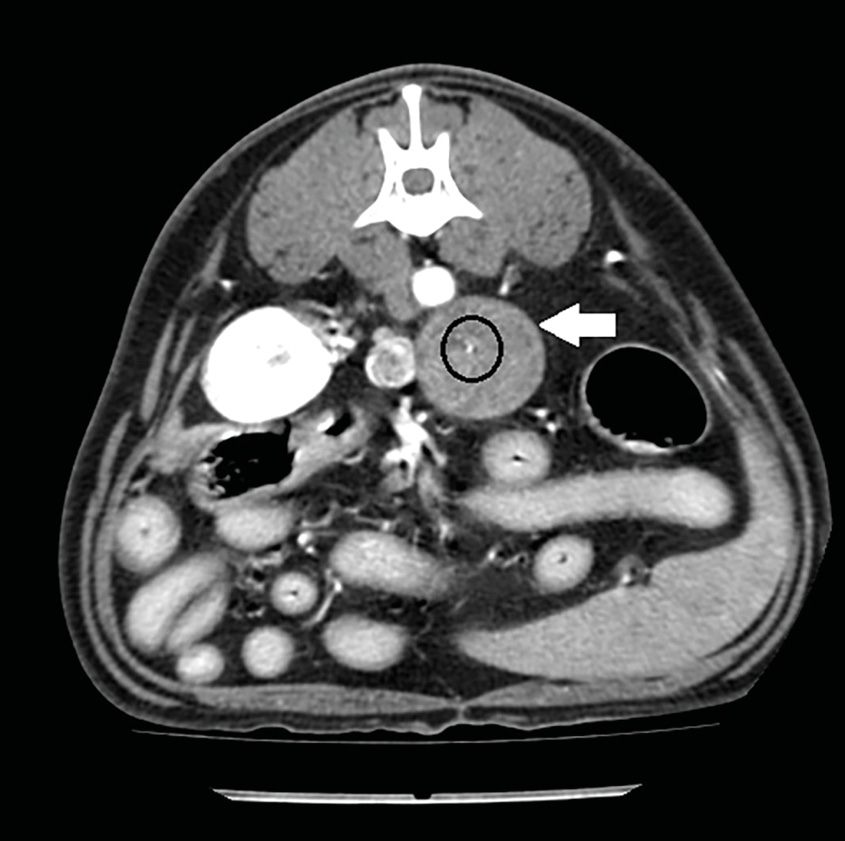

En estudios de TC sin contraste los feocromocitomas se observaron con valores más altos de Unidades Hounsfied (UH) con una atenuación media de 44,5 UH mientras que, en los adenocarcinomas, se observaron valores precontraste más bajos28,29. Esto puede deberse a que estos últimos se asocian con una mayor necrosis del parénquima o a que los feocromocitomas presentan con más frecuencia hemorragia intraparenquimatosa29. La angio-TC trifásica puede ayudar también a la diferenciación de las masas adrenales: se ha descrito que los feocromocitomas presentan una rápida captación de contraste en la fase arterial (imagen 6), mientras que los adenocarcinomas presentan un mayor realce en la fase venosa (imagen 7) y los adenomas un realce homogéneo en la misma fase32.

Imagen 6. Imágenes de TC plano transversal en ventana de tejidos blandos tras la administración de contraste en fases arterial (A) y venosa (B) de un feocromocitoma donde se observa un marcado realce en la fase arterial que disminuye y se vuelve más homogéneo en la fase venosa.

Imagen 7. Imágenes de TC en plano transversal en ventana de tejidos blandos sin contraste (A) y tras la administración de contraste en fase venosa (B) de un adenocarcinoma (flecha blanca) donde se observa un punteado hiperatenuante compatible con mineralizaciones (círculo). Tras la administración de contraste presenta el mayor realce en la fase venosa.